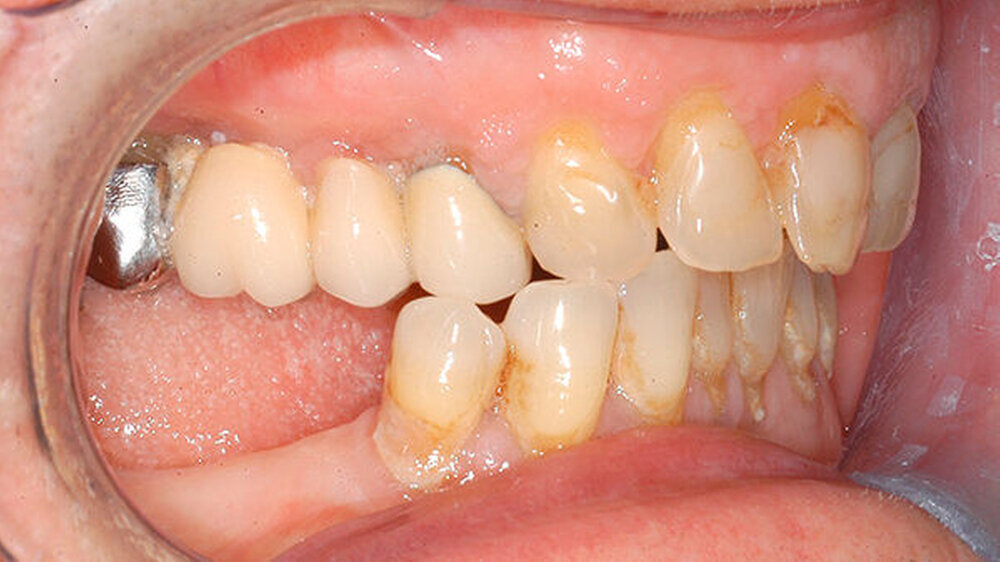

Eine Woche nach Abschluss der internistischen Therapie stellte sich die Patientin zur Verlaufskontrolle in unserer Klinik vor, dabei zeigte sich eine vollständige Remission der hyperplastischen Gingiva bei weiterhin insuffizienter Mundhygiene (Abbildungen 4 und 5).